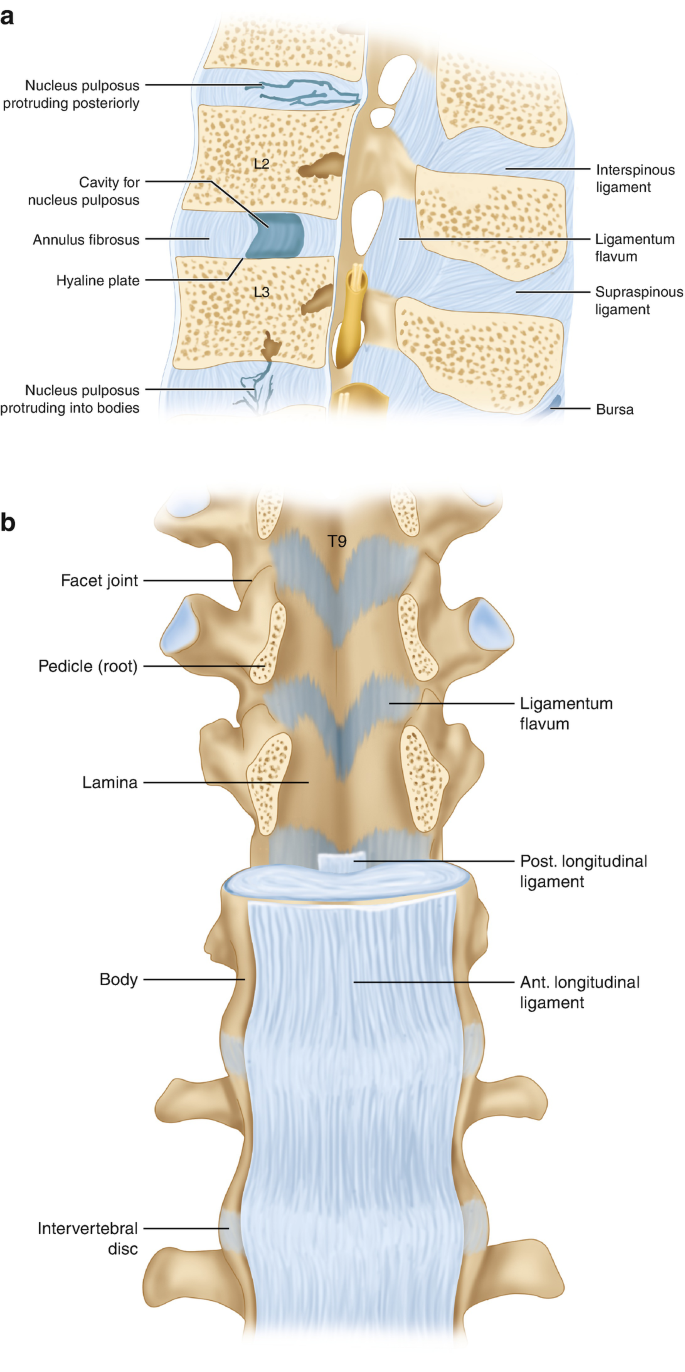

Pure Health - Anatomy 101 - Supraspinous ligament and interspinous ligament 📚 The supraspinous ligament and interspinous ligament work together to limit flexion of the spine by limiting separation of the spinous

DOCS - The interspinous ligament is located between the spinous processes of adjacent vertebrae in the spine. It extends from the base of one spinous process to the apex of the next,

The vertebral column usually contains three curves. The cervical and lumbar curves are convex anteriorly, and the thoracic curve is convex posteriorly. These curves, together with gravity, barricity of the local anesthetic,